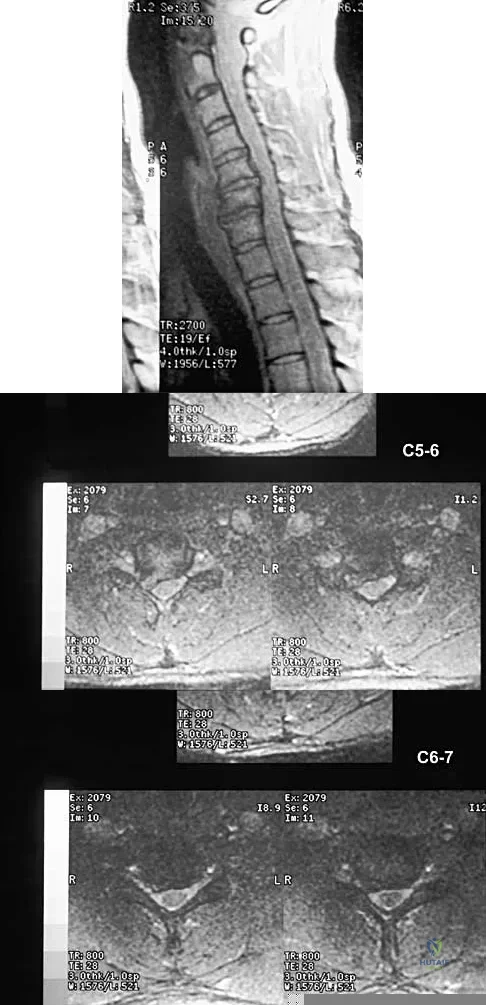

A 40-year-old carpenter has a 3-month history of right arm pain and neck pain that now leaves him unable to work. Examination reveals a positive Spurling test, weakness of the biceps, and a mildly positive Hoffman's sign on the right side. Electromyography and nerve conduction velocity studies show a right C6 deficit. Figures 27a through 27c show MRI scans that reveal two-level spondylotic disease at C5-6 and C6-7, a large herniated nucleus pulposus at C5-6, and a prominent ridge and hard disk at C6-7. Nonsurgical management fails to provide relief, so the patient elects surgical intervention. Which of the following surgical options would give the best long-term results?

Explanation